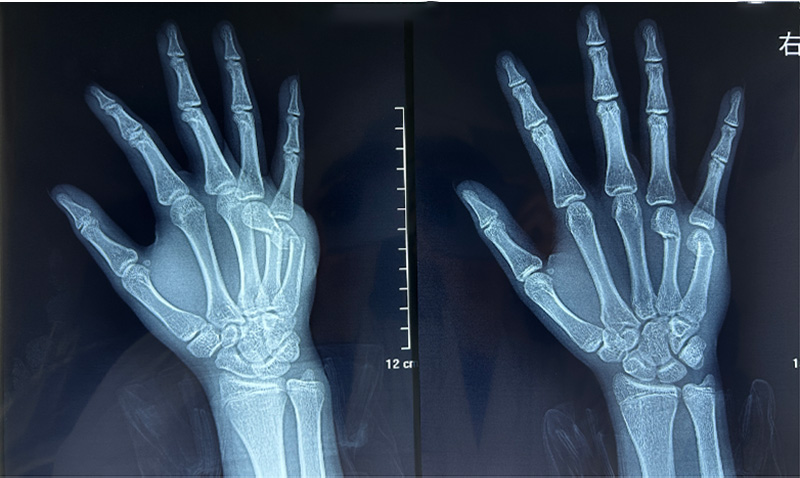

第一个病例是一位13岁的少年。患者因摔伤导致右手第4、5掌骨骨折,入院时右手部肿痛、畸形,活动受限已达30分钟。骨三科团队迅速响应,在神经阻滞麻醉下为患者急诊实施了“右手第4、5掌骨骨折闭合复位内固定术”。术中无需大切口,既精准复位了骨折断端,又最大程度保护了手部功能与外观,为年轻患者的早日康复奠定了坚实基础。

术前